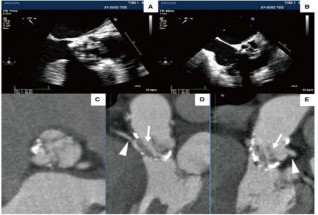

Năm 2019, Tada N và cs đã báo cáo trường hợp thay van ĐMC qua đường ống thông đầu tiên trên bệnh nhân sau mổ tái tạo van ĐMC bằng MNT tự thân theo phương pháp Ozaki. Đây là trường hợp bệnh nhân nam 80 tuổi, được phẫu thuật tái tạo van ĐMC bằng MNT tự thân theo phương pháp Ozaki cách 5 năm. Bệnh nhân được chẩn đoán hẹp van ĐMC đã tái tạo bằng MNT do lá van dài, dày và vôi hoá mép van (Hình 1.22). Bệnh nhân đã được tiến hành thành công thay van ĐMC qua đường ống thông (Hình1.23), kết quả

theo dòi sau 1 năm diện tích hiệu dụng của van 1,89 cm² và chênh áp trung bình qua van là 8 mmHg.69

Hình 1.22. Hình ảnh siêu âm tim (A, B) và chụp cắt lớp vi tính của bệnh nhân sau mổ tái tạo van động mạch chủ 5 năm.69